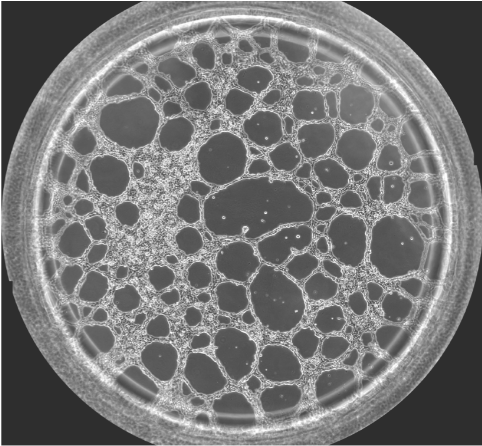

圖一 血管生成鏡檢圖

無論原發(fā)性腫瘤還是繼發(fā)性腫瘤,一旦生長直徑超過1~2 mm,都會(huì)有血管生成。這是由于腫瘤細(xì)胞自身可分泌多種生長因子,誘導(dǎo)血管生成。多數(shù)惡性腫瘤的血管生成密集且生長迅速。因此,血管生成在腫瘤的發(fā)展轉(zhuǎn)移過程中起到重要作用,抑制這一過程將能明顯阻止腫瘤組織的發(fā)展和擴(kuò)散轉(zhuǎn)移。于是體外的血管生成實(shí)驗(yàn)就能很好的模擬腫瘤的血管發(fā)生過程,并且適合研究藥物對(duì)這一過程的影響實(shí)驗(yàn)。本實(shí)驗(yàn)以HUVEC細(xì)胞為例,介紹這一實(shí)驗(yàn)的詳細(xì)過程。